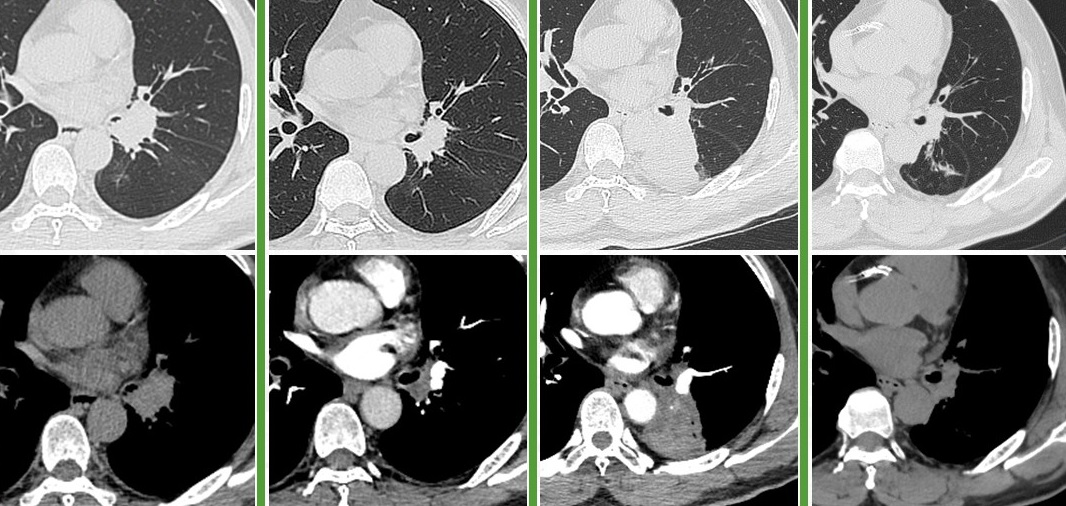

图:左起依次为基线、免疫联合化疗4周期后、末次随访

图:左起依次为三线治疗前、三线治疗后、四线治疗前、末次随访